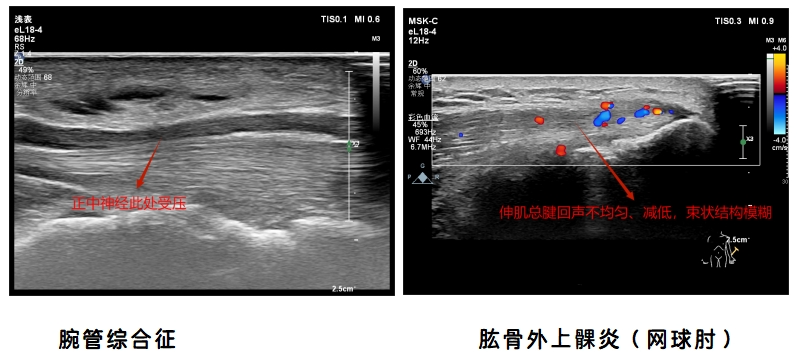

让我们一起看一下肌骨超声图像吧

2.肘关节超声检查:肘管综合征、肱骨内上髁炎(高尔夫球肘)、肱骨外上髁炎(网球肘)、尺骨鹰嘴滑囊炎等。

3.腕关节超声检查:腕管综合征、桡骨茎突狭窄性腱鞘炎(妈妈手)、扳机指、类风湿性关节炎、拇长屈肌腱断裂、前臂交叉综合征等。